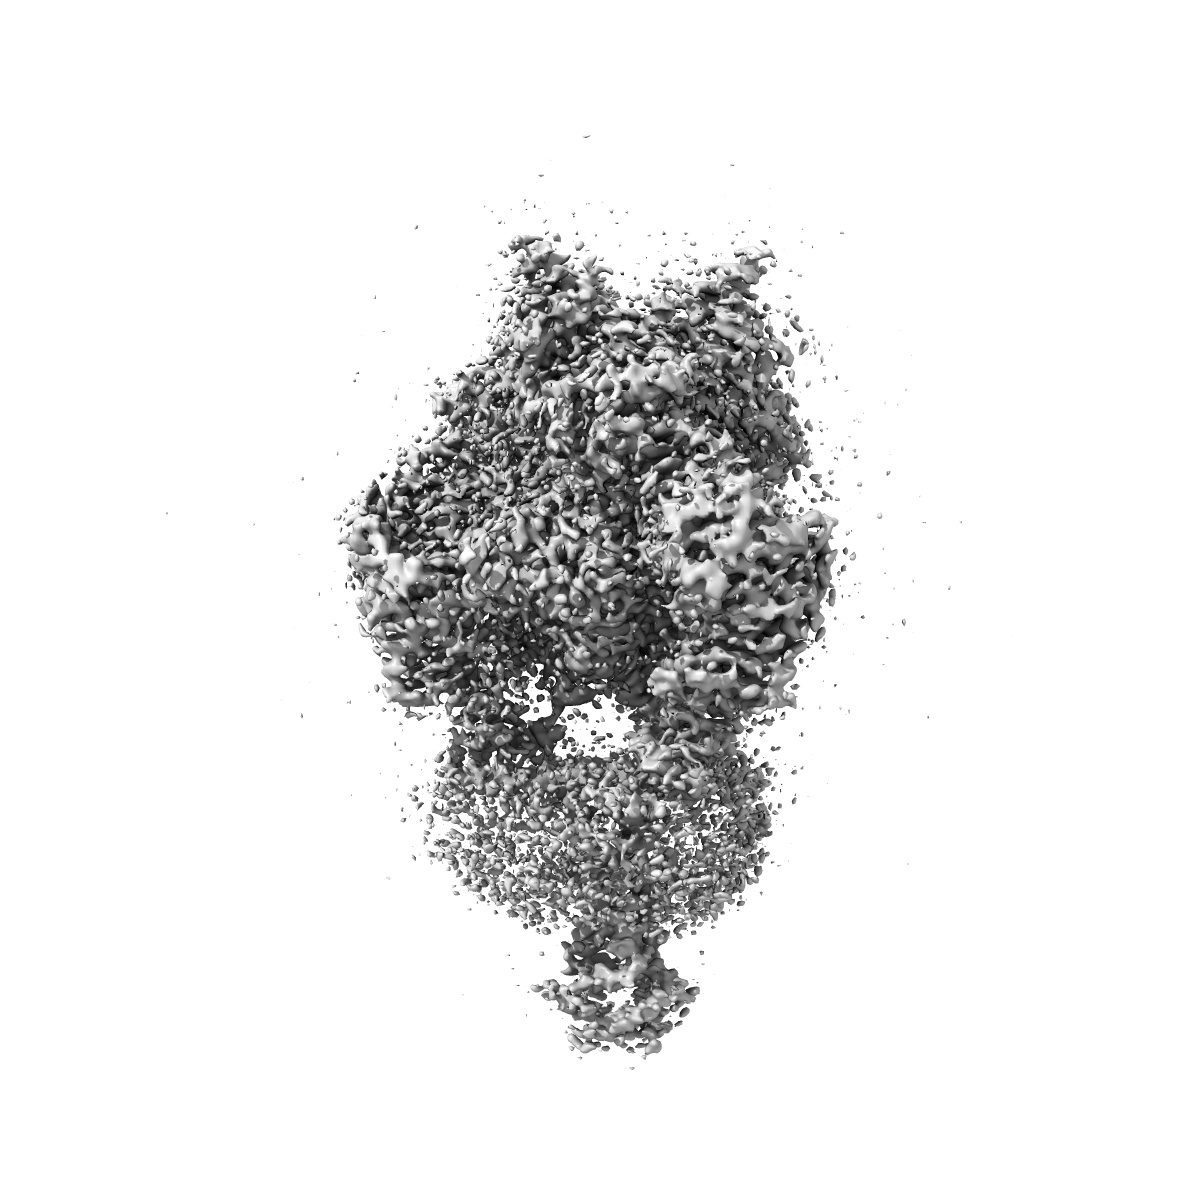

HSV-1 prefusion glycoprotein B

Single-particle2.64 Å

Sample: Human alphaherpesvirus 1 Glycoprotein B

A nanobody specific to prefusion glycoprotein B neutralizes HSV-1 and HSV-2.

(2025) Nature , 646 , 433 - 441